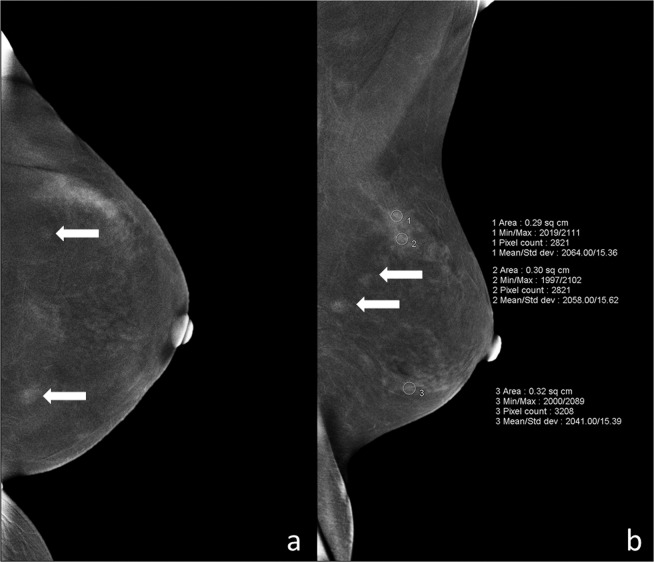

BPE—The extent of BPE was categorized subjectively using both CC and MLO views. In the absence of a recognized CESM lexicon, the volume and intensity of enhancement were categorized according to the BI-RADS MRI grading system as: level a = minimal; level b = mild; level c = moderate; level d = marked (Fig. 1). The intensity of enhancement was measured quantitatively using a region-of-interest (ROI) of about 0.3 cm2 placed manually over the area with the most enhancement within the BPE on the last MLO image, while avoiding blood vessels and the pectoralis major muscle. The maximum, minimum, and difference pixel values were recorded. For BPE level (see below) a and b subjects, the ROI was placed three times at the area with most obvious BPE; for level c and d subjects, the ROIs were placed at three areas with obvious BPE (Fig. 2). For subjects with lesions encountered incidentally on the last MLO image, the area for BPE measurement was selected so as to avoid abnormal enhancement around the lesion or more than 1 cm from the lesion (Fig. 3). For lesions observed on ultrasound but not on CESM, the ROI was not placed at the location of the lesion on ultrasound.

Figure 3.

BPE measurement in an ROI placed more than 1 cm from the lesions for subjects with accidental lesions on the last MLO image. (a) Contralateral craniocaudal (CC) iodine-specific images in this 45-year-old woman with a history of a palpable mass in the right breast show two enhanced masses (white arrows) in the left breast. (b) Contralateral mediolateral oblique iodine-specific images show BPE level as c, and the ROI placed more than 1 cm from the lesions (white arrows). BPE, background parenchymal enhancement; ROI, region-of-interest; CC, craniocaudal; MLO, mediolateral oblique.